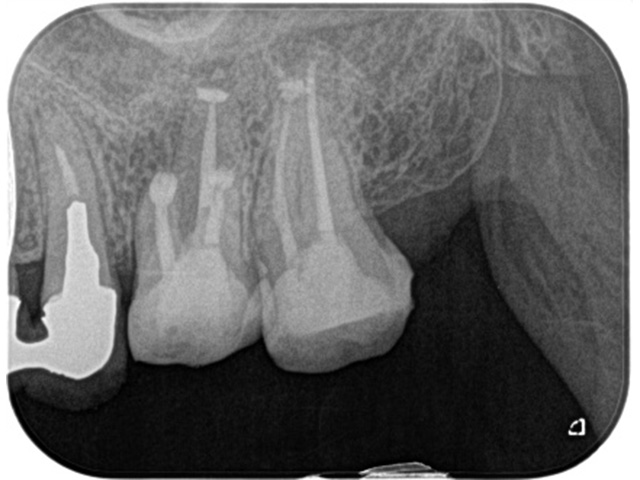

術前(主訴は左上の奥歯の歯ぐきの腫れが気になるということでした)

左上の第一大臼歯および第二大臼歯をラバーダムというゴムのマスクを使用して無菌的な環境の中で歯の神経の治療を行いました。

根管治療終了後のレントゲン写真です。

根の先までお薬を詰めることができましたが1か月後歯ぐきの腫れが再発したため患者さまとご相談し意図的再植術を行い感染源の除去を行うことしました。

① 隣の歯に負担をかけないように事前に水色のゴムを入れて歯と歯の間を開きます

② 一度原因歯を抜去します

③ 抜いた歯を口腔外で視診し根が折れていないか確認します。

そのあと歯根の先の部分を口腔外で3ミリ程度切断し、裏側からMTAセメントというセメントを詰めて口腔内に戻し、縫合した後レントゲン写真を撮影します。

現在歯ぐきの腫れも、歯の痛みもなく経過良好です。

手前の歯については患者さまのご希望により経過観察中です。

| 主訴 | 左上の奥歯の歯ぐきが腫れて違和感が続いている |

|---|---|

| 治療内容 | 左上第一大臼歯および第二大臼歯の根管治療(ラバーダム防湿下)及び左上第一大臼歯の意図的再植術 |

| 治療回数・期間 | 6回 内訳【根管治療:3回(2歯合わせて)、意図的再植術:1回、被せものの作成:2回】 |

| 費用 | 保険適応 |

| リスク・副作用 | 根管治療は術前の精密な診査診断およびラバーダム防湿を用いた無菌環境下での治療によって成功率は高まってきましたが治療の成否を決める多くの要素があるため、根管治療がなされた後も再治療や外科処置、抜歯となる可能性が少なからずあります。また治療中には器具の破折や穿孔、修復物の損傷、歯の破折、術中・術後の痛みや腫れが生じることが稀にあります。根尖病変(再感染)を防ぐには適合の良好な補綴物を作製することや定期的なかみ合わせのチェックが必要です。 |